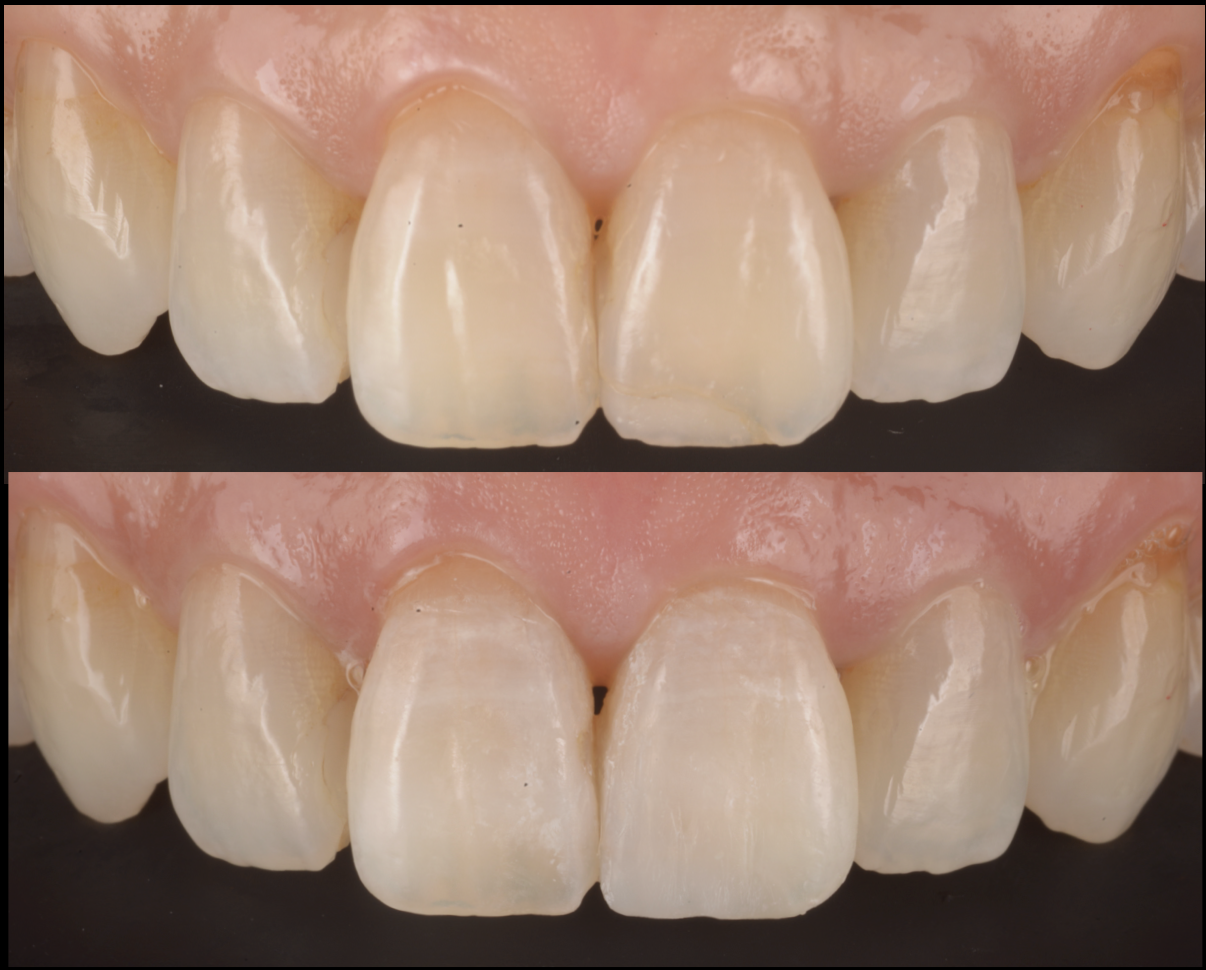

🦷 1. 症例紹介:歯がすり減って磨耗したケース【...